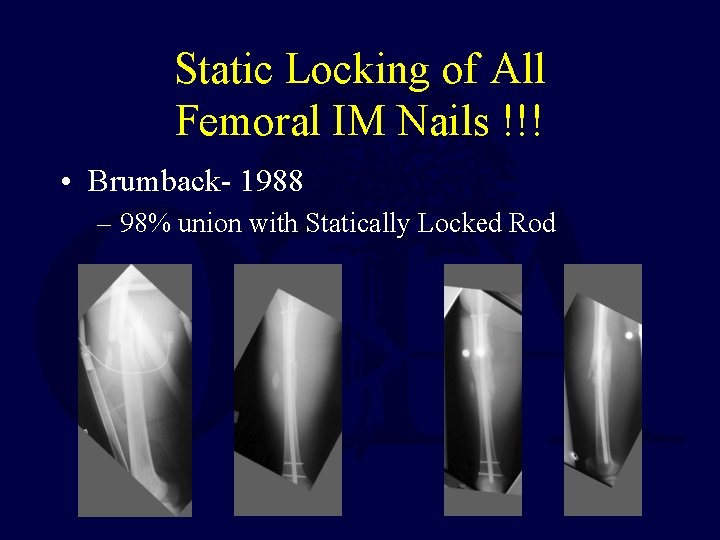

Static Locking of All Femoral IM Nails !!! • Brumback- 1988 – 98% union with Statically Locked Rod